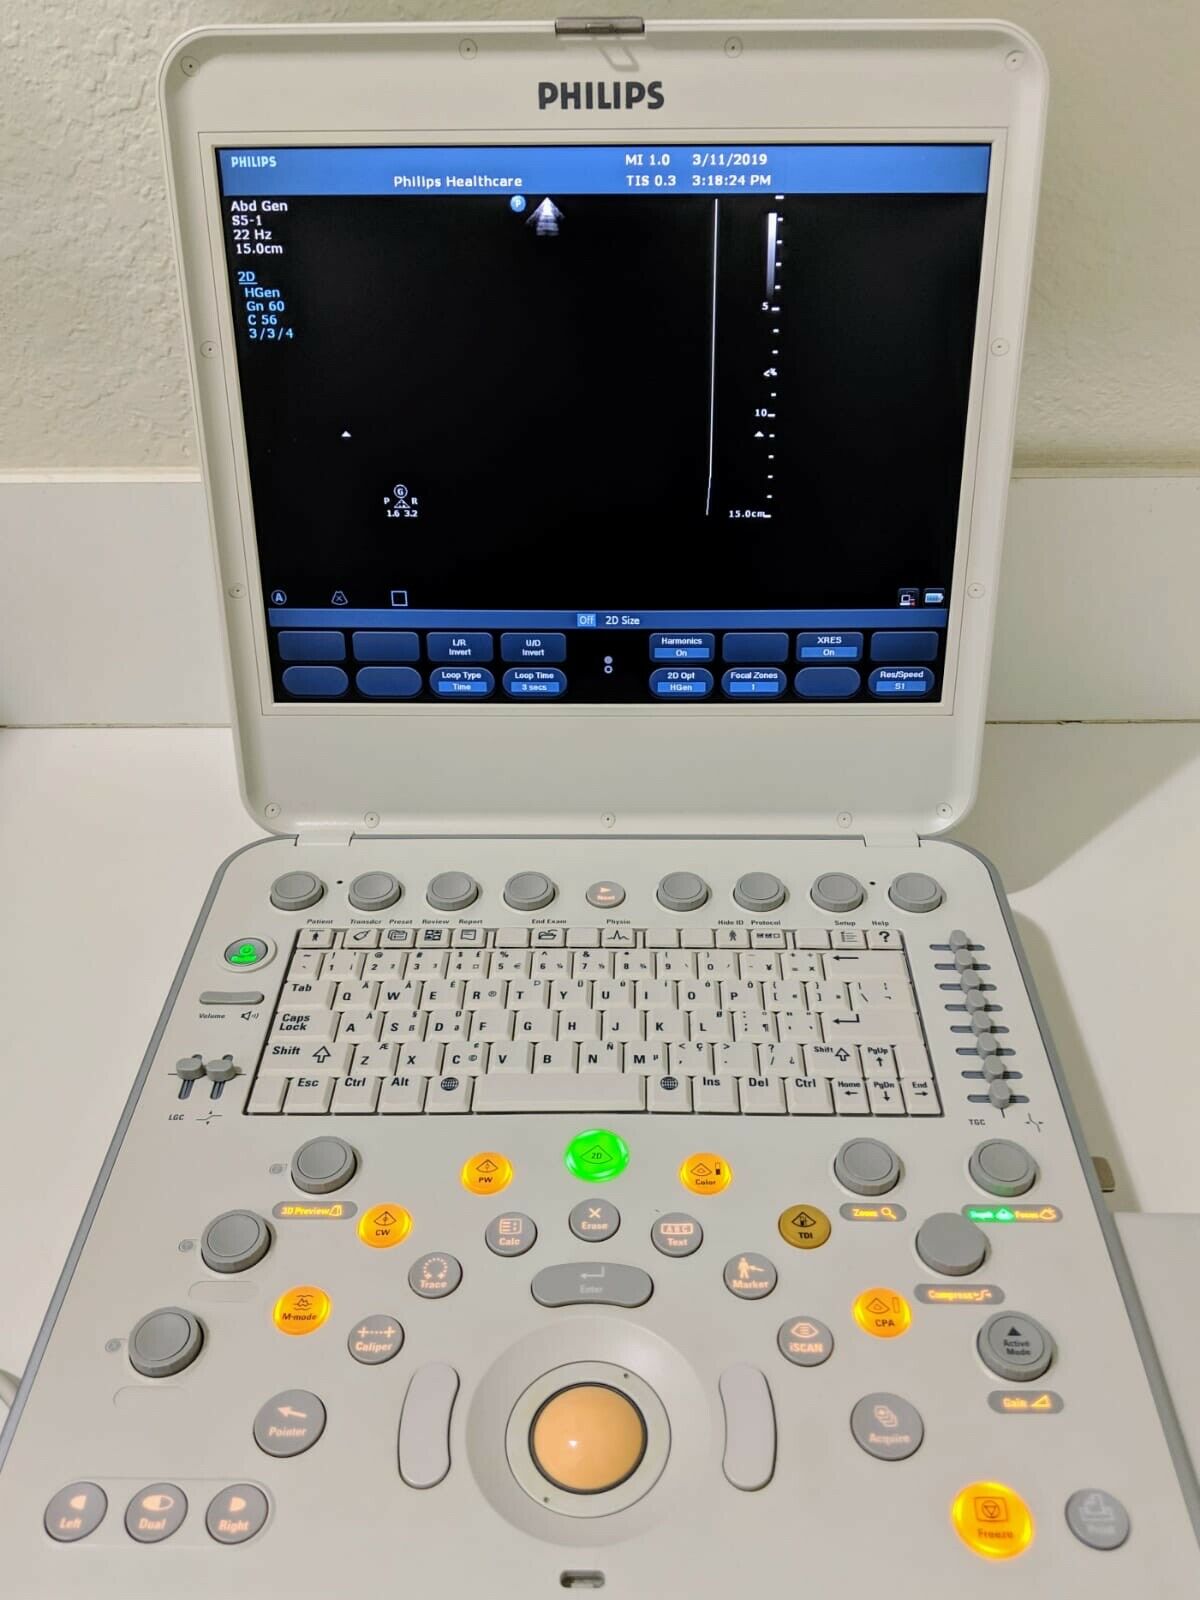

The Philips CX50 2013 Rev 4 Portable Ultrasound System with three probes is a high-performance imaging solution designed for flexibility across a range of clinical applications. This compact, portable ultrasound machine delivers premium imaging quality, making it ideal for point-of-care, cardiology, vascular, and emergency medicine. Equipped with Philips’ advanced imaging technologies like PureWave crystal technology, the CX50 provides exceptional resolution and detail, even in difficult-to-image patients.

The three included probes offer versatility, allowing clinicians to perform various exams, from cardiac and vascular to abdominal and superficial imaging. Its portability and lightweight design make it easy to transport between departments or use in field settings, without compromising on diagnostic accuracy. The CX50’s intuitive interface and customizable presets streamline workflows, making it user-friendly for fast-paced environments. This system is an excellent choice for healthcare providers needing a portable ultrasound solution that offers advanced imaging capabilities and multi-specialty support.